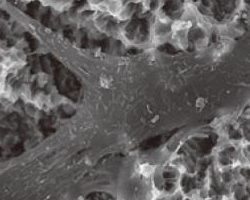

Скенираща електронна микроскопия на витален остеобласт, разположен върху имплантатната повърхност. Именно това представлява процесът на остеоинтеграция, който е от ключово значение за успеваемостта и трайността на лечението с импланти. Тъй като зъбни импланти се поставят масово в световен мащаб от началото на 60-те години на ХХ век, вече има натрупан огромен клиничен опит и дългогодишни наблюдения върху всички процеси в областта на костта и меките тъкани. Отдавна има доказателства че при правилно проведени лечебни процедури и добър оздравителен процес имплантът се интегрира трайно и плътно към костните тъкани - налице е остеоинтеграция. Това се наблюдава предимно при награпавените имплантатни повърхности и в много по-малка степен при полираните импланти - те се задържат в челюстните кости чисто механично, на принципа на макроретенцията. Въпреки че материалите, от които се изработват имплантите, всъщност са едни и същи (предимно чист титан), наличието на микрограпавини силно подобрява адаптацията на импланта към костните тъкани. Почистването на тези микрограпавини обаче е технически трудно - в случай че възникне проблем. Поради това при развитие на възпаление (периимплантит) прогресията е доста по-бърза и обширна в дълбочина и на ширина. При полираните зъбни импланти чрез хигиенни процедури е възможно да се осигури известно стациониране и дори спиране на процеса - което обаче изисква изключително постоянство и упоритост от страна на пациента.